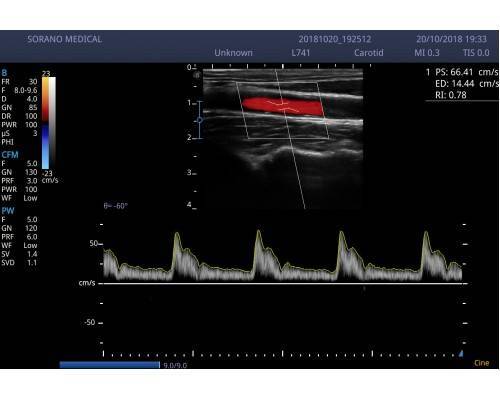

και η λειτουργιά του χρώματος θα σας βοηθήσει στην αποτελεσματικότερη διάγνωση των λαβών.

Προηγμένες τεχνολογίες όπως m-scan,compound, THI,auto trace, auto IMT

(αυτόματος εντοπισμός πάχυνσης ενδοθηλίου καρωτίδας) με ενσωματωμένη μπαταρία.

• Εικόνα 2 διαστάσεων 2D (B mode),2B(δίπλες εικόνες), 4B(τετραπλές εικόνες), M mode, PW (pulse wave Doppler,CFM (color),PDI(power)DirPDI (κατεύθυνση ροής )CW .

• PW auto trace (αυτόματες μετρήσεις pulse wave Doppler)

L741 (VASCULAR-SMALL PARTS-MSK) 4.0-16.0 MHZ 46mm